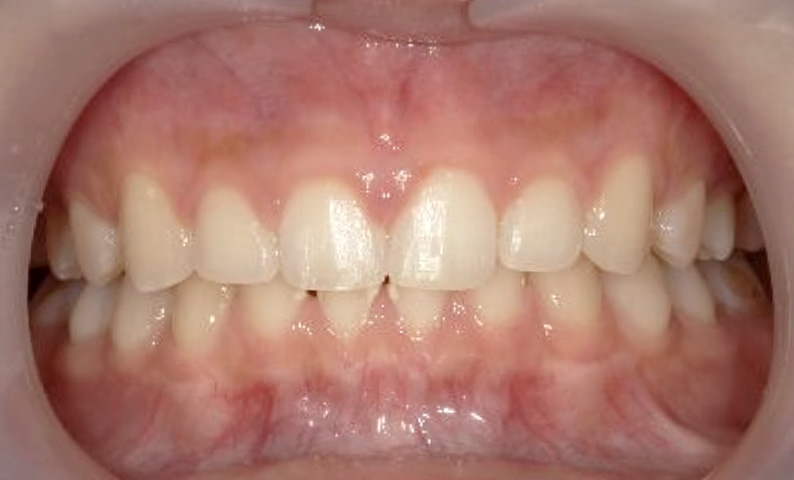

症例_025 上下顎の部分矯正

治療期間:13ヶ月金額:51万円+税女性前歯のガタガタ出っ歯

| Before | After |

|---|---|

|